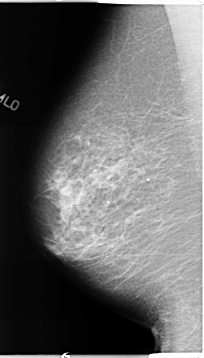

B_3123_1.RIGHT_MLO

RIGHT_CC LINES 4640 PIXELS_PER_LINE 2336 BITS_PER_PIXEL 12 RESOLUTION 50 NON_OVERLAY

RIGHT_MLO LINES 4648 PIXELS_PER_LINE 2640 BITS_PER_PIXEL 12 RESOLUTION 50 NON_OVERLAY